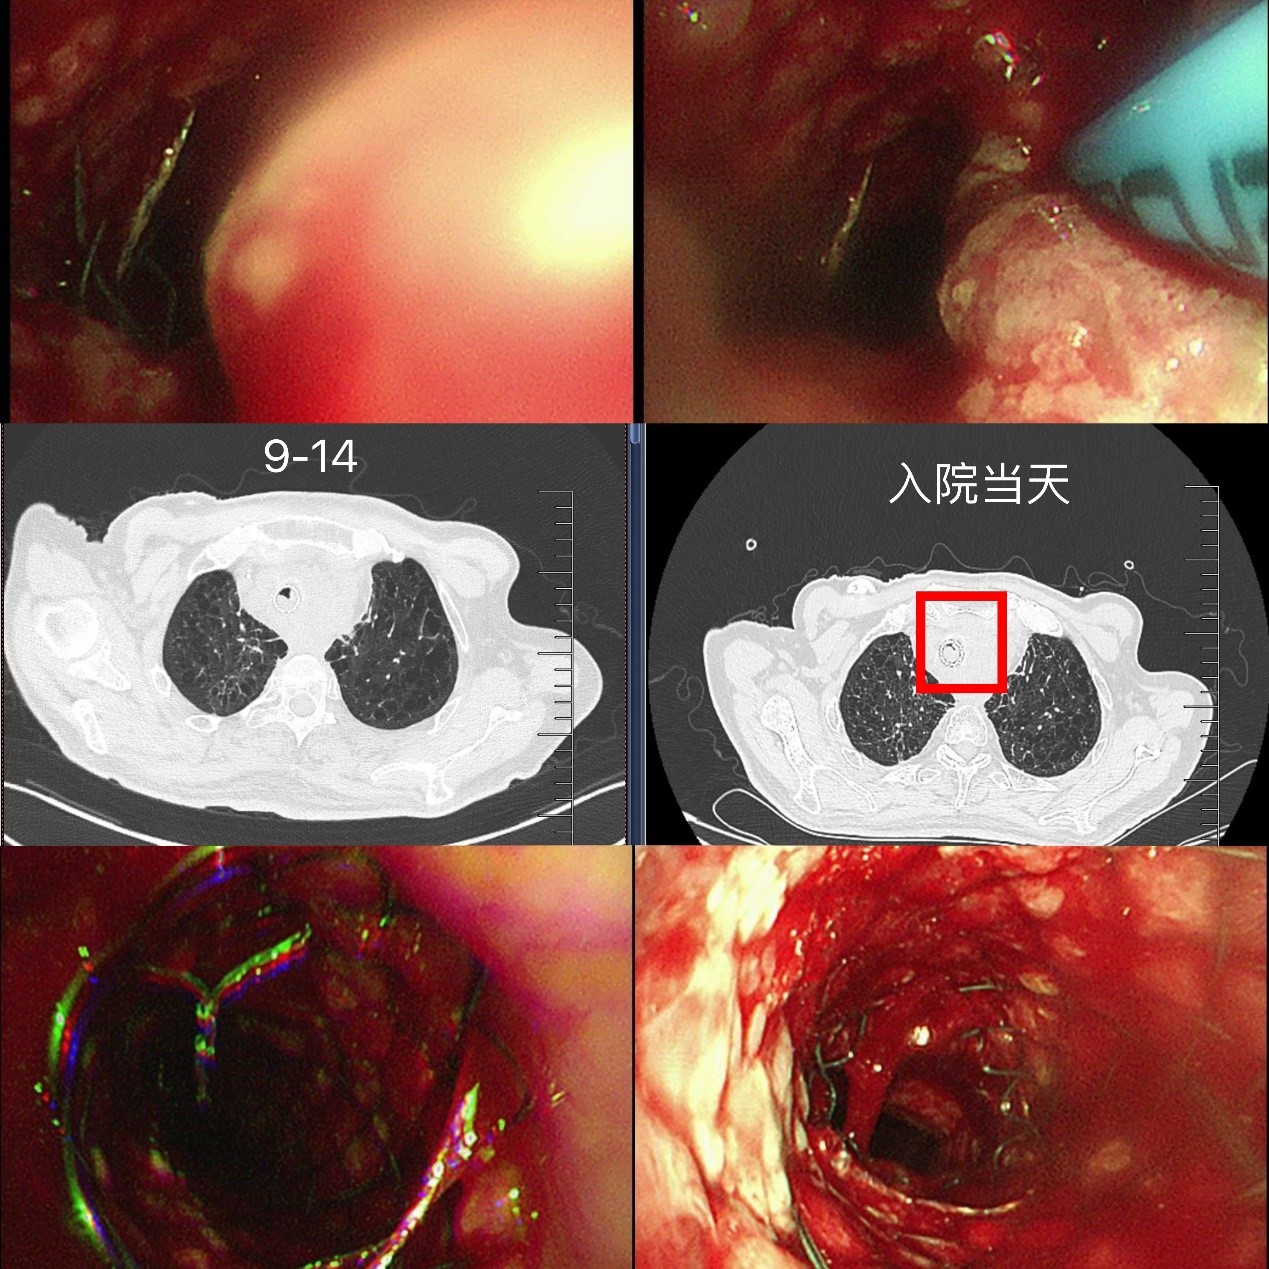

尽管龚先生尝试了一些治疗,但病情的进展远超预期。320日,因纵隔肿物持续压迫气管,他出现严重胸闷、气急,被紧急送往苏大附四院呼吸与危重症医学科。入院时动脉血气分析提示I型呼吸衰竭(重度),氧饱和度持续走低,呼吸微弱,生命体征岌岌可危。

“患者气道狭窄已达90%,必须立刻干预!”蒋军红主任第一时间评估病情,果断启动紧急救治方案:予无创呼吸机辅助通气维持氧供,同时用哌拉西林钠他唑巴坦、左氧氟沙星抗感染,伏立康唑针对性抗黄曲霉菌,甲泼尼龙减轻气道炎症,并同步调控血压、血糖,雾化化痰等综合治疗。

迅速排除手术禁忌,蒋军红主任团队为龚先生实施“支气管镜下主支气管支架置入术”。术中可见声门下4cm处气管呈混合性狭窄,狭窄长度约2cm,团队精准定位后,成功置入一枚16×40mm金属裸支架。术后2天复查气管镜,支架贴壁良好,仅少量肿瘤从网眼生长,经APC消融治疗。龚先生的胸闷、气喘明显缓解,顺利出院继续后续肿瘤治疗。